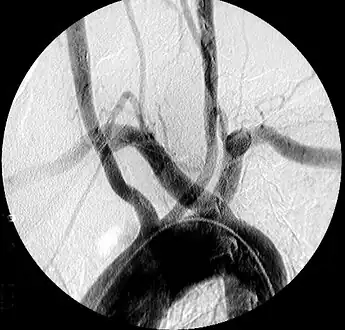

Aberrant right subclavian artery at angiography.